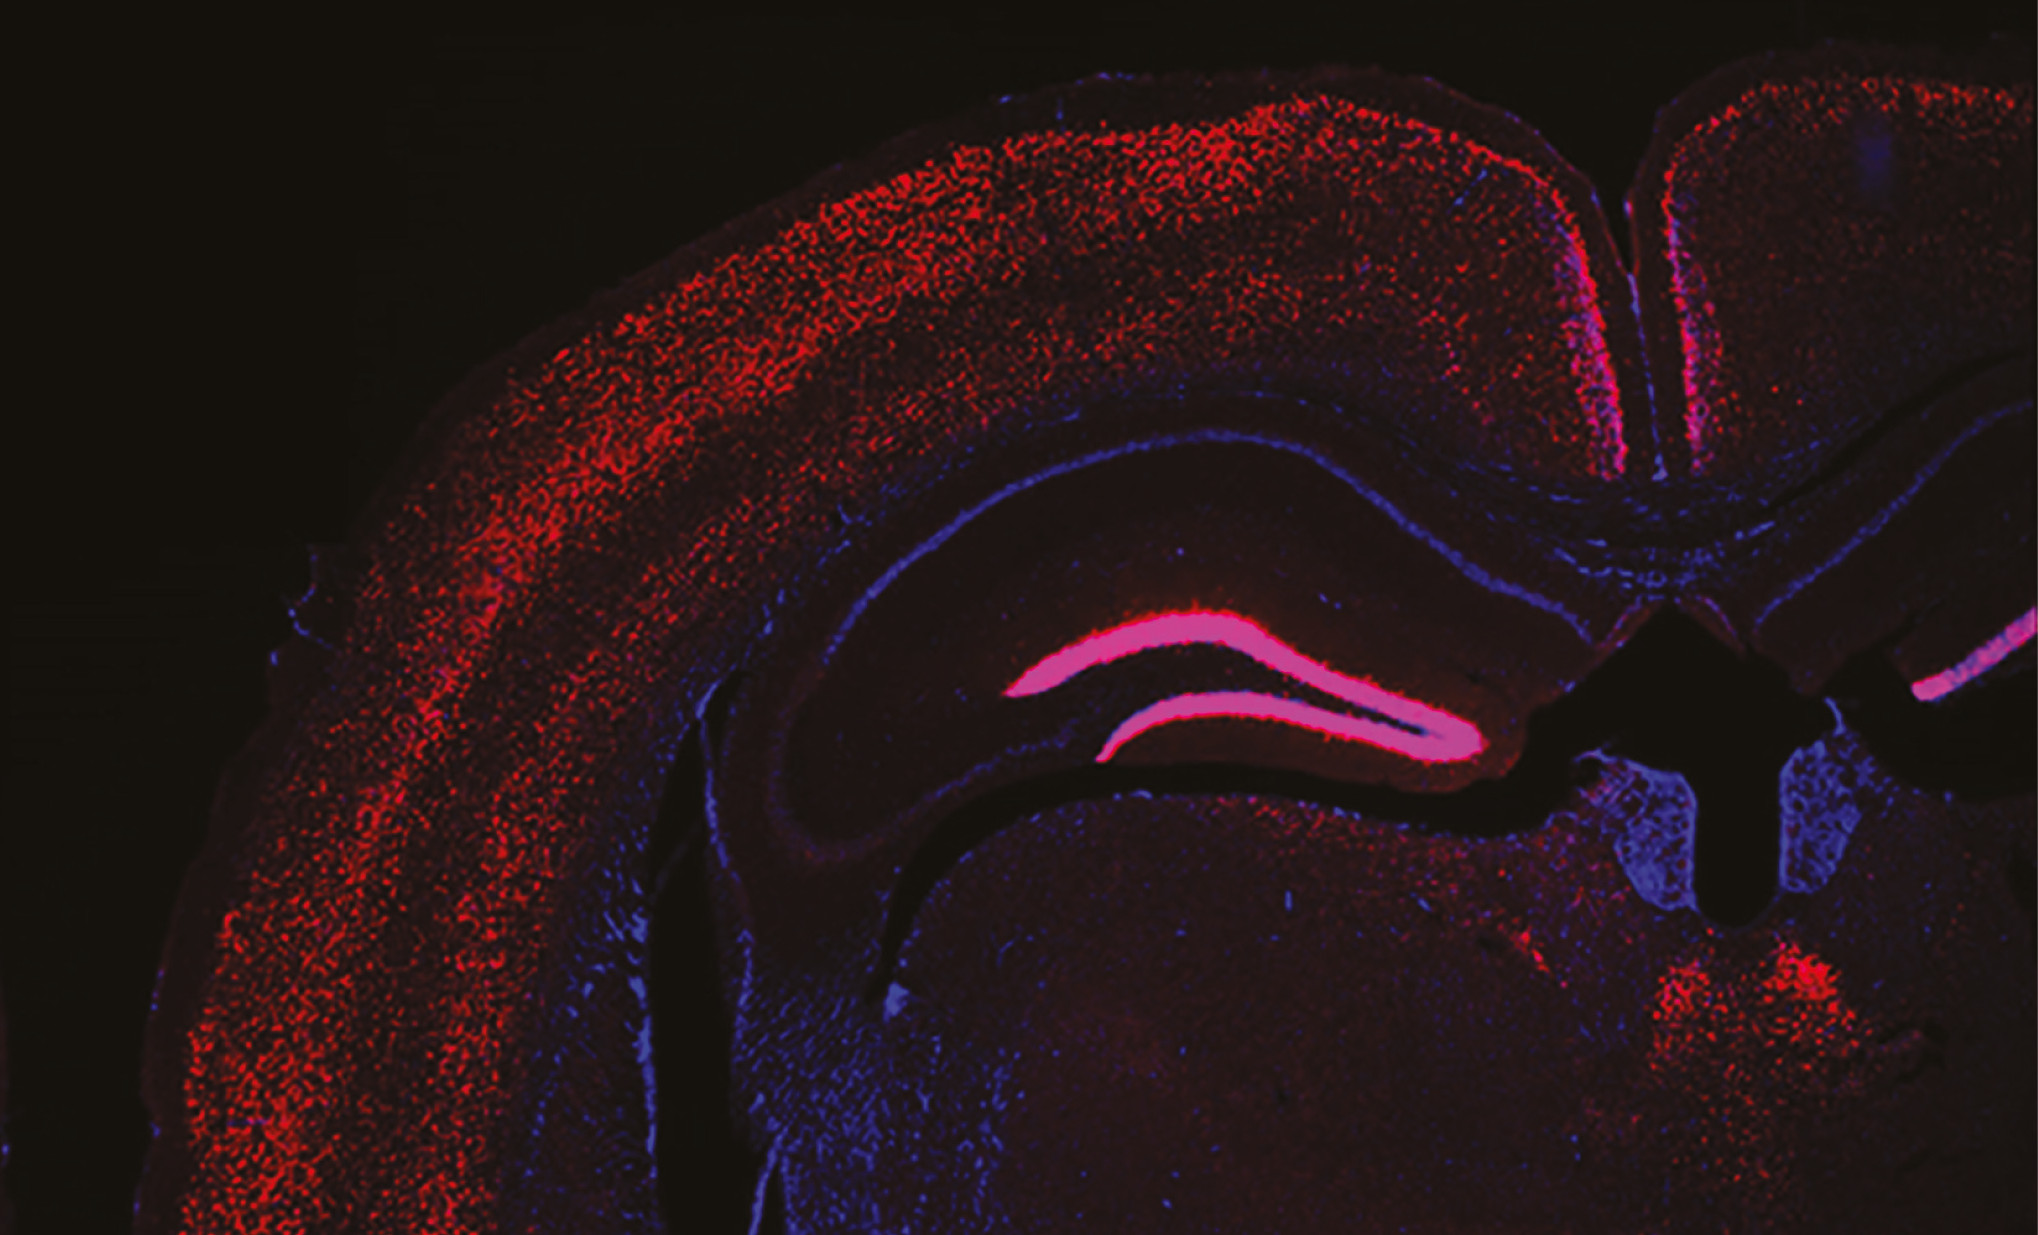

Mitochondrial epilepsy could originate in a specific group of brain neurons

A team led by Dr Albert Quintana has for the first time identified the mechanism behind a potentially fatal type of epilepsy, a symptom of mitochondrial diseases. The discovery, based on mice models, challenges the traditional idea that these disorders are caused by a generalised energy deficiency and instead reveals a precise disfunction in specific brain circuits.